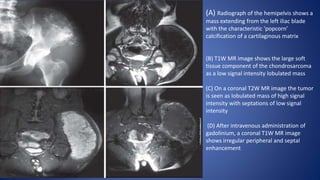

(A) Radiograph of the hemipelvis shows a

mass extending from the left iliac blade

with the characteristic ‘popcorn’

calcification of a cartilaginous matrix

(B) T1W MR image shows the large soft

tissue component of the chondrosarcoma

as a low signal intensity lobulated mass

(C) On a coronal T2W MR image the tumor

is seen as lobulated mass of high signal

intensity with septations of low signal

intensity

(D) After intravenous administration of

gadolinium, a coronal T1W MR image

shows irregular peripheral and septal

enhancement